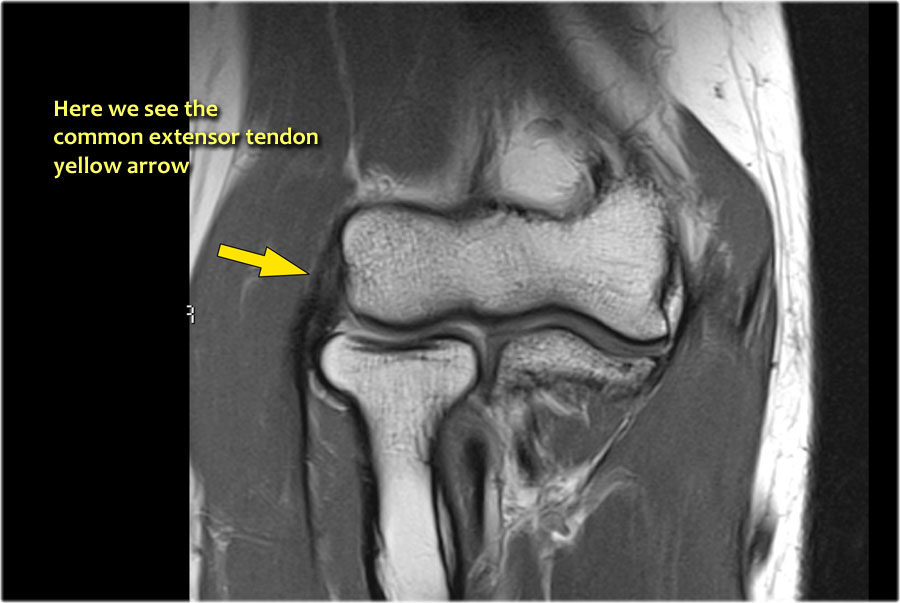

Common Extensor Tendon

Gân duỗi chung xuất phát từ mỏm trên lồi cầu ngoài.

Trên ảnh T1W, gân phải có tín hiệu thấp (mũi tên vàng).

Lateral Epicondylitis

Viêm lồi cầu ngoài còn được gọi là khuỷu tay tennis, mặc dù trong 95% trường hợp được gặp ở những người không chơi tennis.

Nguyên nhân là do căng thẳng mãn tính lên gân duỗi chung, dẫn đến rách một phần và thoái hóa gân.

Thông thường, cơ duỗi cổ tay quay ngắn là thành phần bị ảnh hưởng.

Trong các trường hợp nặng hơn, có sự rách của dây chằng bên ngoài (LCL), cho thấy đáp ứng kém với điều trị bảo tồn.